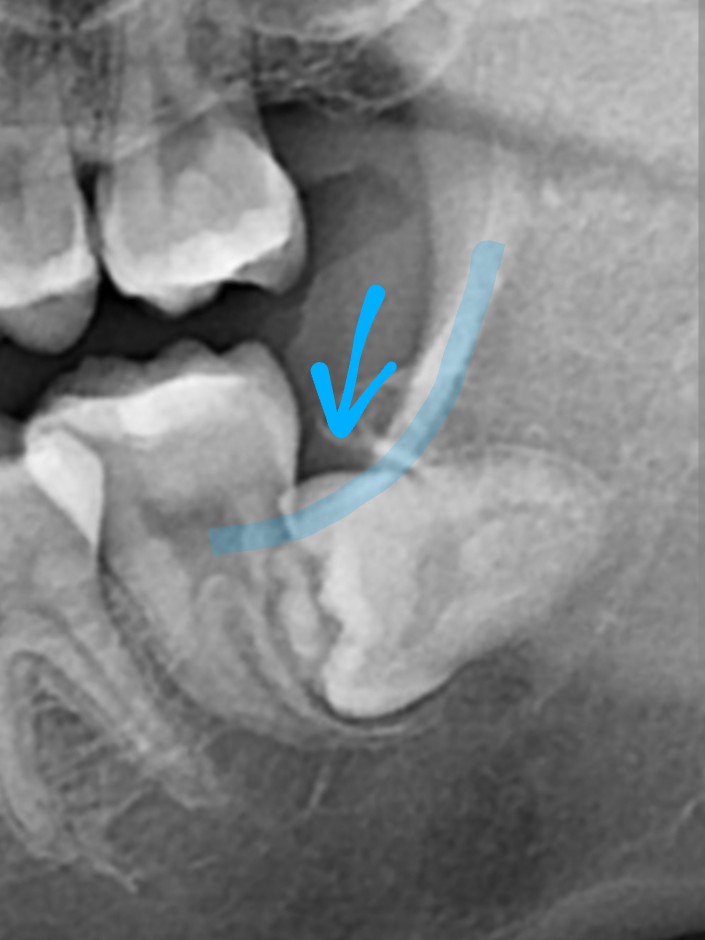

skyyo : 也有冒小角的水平智齒 下圖是網路牙 39.12.73.25 10/07 15:34

skyyo : 醫診所的類似案例 39.12.73.25 10/07 15:34

skyyo : http://i.imgur.com/p1FKj38.jpg 39.12.73.25 10/07 15:34